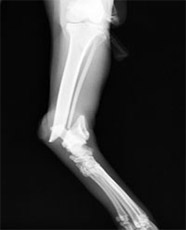

後肢脛腓骨骨折

この箇所は犬、猫とも認められますが、あまり多くはみられません。交通事故が多くの原因ですが、後ろ足が引っかかって無理に引っ張った時に骨折することもたまにあります。

手術前

手術後

脛骨遠位側の骨折です。今回はプレート、スクリューで治療しましたが、創外固定などを使用する場合もあります。